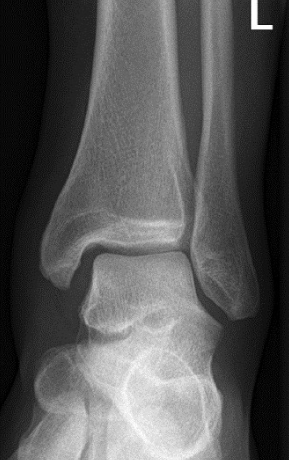

Q

error

A

external rotation